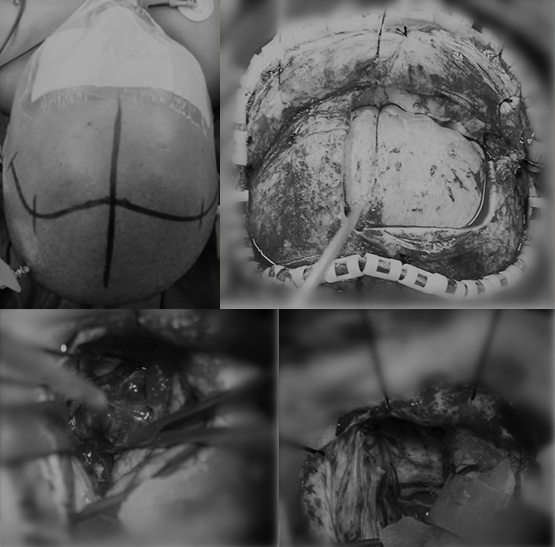

术中可见

肿瘤位于鞍窝及鞍上及前颅底处,肿瘤大小约4*5*5厘米,灰红色,边界尚清,肿瘤卒中,肿瘤质地较韧,血供丰富,肿瘤与垂体柄、双侧视神经、视交叉、双侧大脑前动脉、双侧颈内动脉粘连。

术中图片

肿瘤位于鞍窝及鞍上区,肿瘤大小约3*2.5*3厘米,肿瘤呈囊实性,囊液为灰黑色粘稠液体,实质部分呈灰黄色,质地较韧,部分钙化,囊壁与垂体柄、下丘脑和双侧视神经、视交叉、颈内动脉粘连。其中与垂体柄粘连紧密。